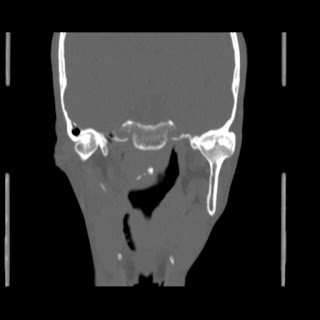

O/E images: